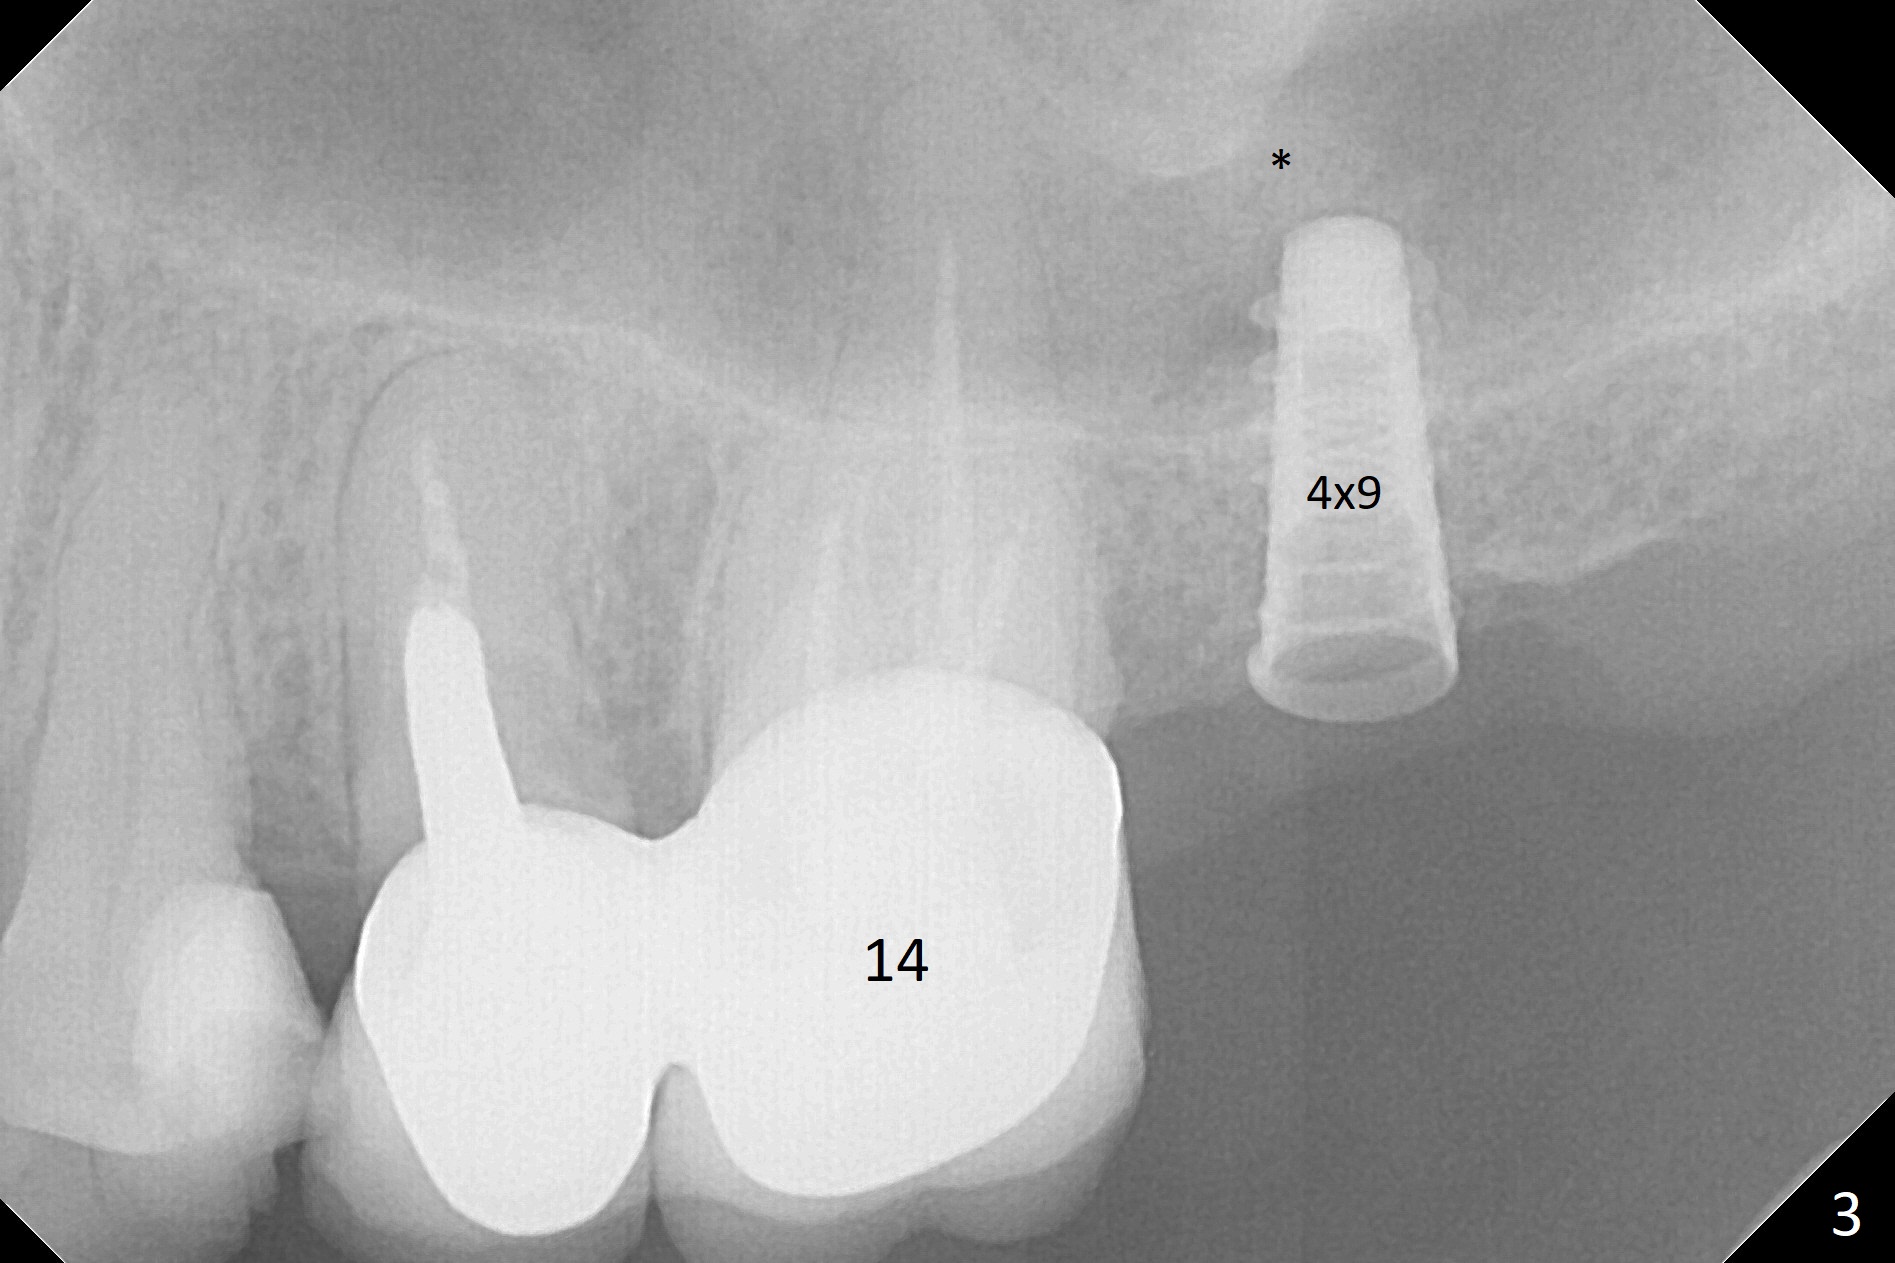

After removal of the mesial (M) and distal (D) residual roots of the tooth #15 (Fig.1,2), Magic Split is used to test bone density (high), followed by Magic Drills from Magic Sinus Lift Kit (for 4 mm) and Magic Surgical Kit (for 5 mm). It appears that the sinus floor has been perforated with the intact sinus membrane. Following minimal use of Magic Lifter, Vanilla Graft is inserted (Fig.3,4 *) and a 4x9 mm dummy implant is placed. After placement of more allograft (Fig.5 *), a 5x7 mm implant is placed with ~ 35 Ncm. With placement of a 5.5x4(2) mm abutment, an immediate provisional is fabricated to close the socket. Six months postop, the bone graft remains in the sinus around the apical end of the implant (Fig.6 *), while there seems no bone loss coronally (Fig.7). In fact there is, as shown later (Fig.8-11 < and lingual (L)). The crown is recemented 6 months post cementation (due to short abutment). The abutment seems to be incompletely seated. When the crown at #14 is reprep following #13 implant, the abutment screw is being untightened, the crown dislodges first. The abutment is confirmed short with more than enough occlusal clearance. After use of 5.5 and 6.0 mm bone profile drills, a 5x4(3) mm abutment is placed with complete seating.